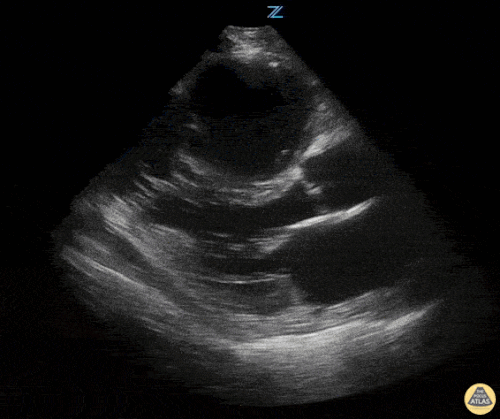

Sağ ventrikül fonksiyonunun değerlendirilmesi

Sağ ventrikül, önceki bölümde anlatılan temel kardiyak pencereler kullanılarak değerlendirilebilir. Normalde sağ ventrikül düşük basınçlı bir odacıktır ve sol ventriküle kıyasla daha küçük görünür.

Sağ ventrikül disfonksiyonunda özellikle şu bulgulara bakılır:

Sağ ventrikül dilatasyonu

Septal bombeleşme (septal bowing)

Kısa aks görüntüsünde, pulmoner arter basıncının artmasına bağlı olarak sağ ventrikül genişledikçe interventriküler septum sol kalbe doğru bombeleşir. Bu durum sol ventrikülde D-şekilli görünüm (D-sign) oluşturur.

Apikal dört boşluk görüntüsünde sağ ventrikül normalde sol ventrikülün yaklaşık üçte ikisi büyüklüğünde olmalıdır. Eğer iki ventrikül aynı boyutta görünüyorsa bu durum anormal kabul edilir ve dilatasyon düşündürür.

Bir diğer önemli bulgu McConnell belirtisidir. Bu bulgu, sağ ventrikül serbest duvarında hipokinezi bulunurken apeksin korunmuş olması şeklinde tanımlanır.

Apikal dört boşluk görüntüsü alınırken dikkatli olunmalıdır. Eğer görüntü aks dışı alınırsa sağ ventrikül kısalmış (foreshortened) görünebilir ve dilatasyon gözden kaçabilir. Bu hatadan kaçınmak için probu hafifçe döndürerek sağ kalbin en geniş göründüğü düzlemi yakalamak gerekir.